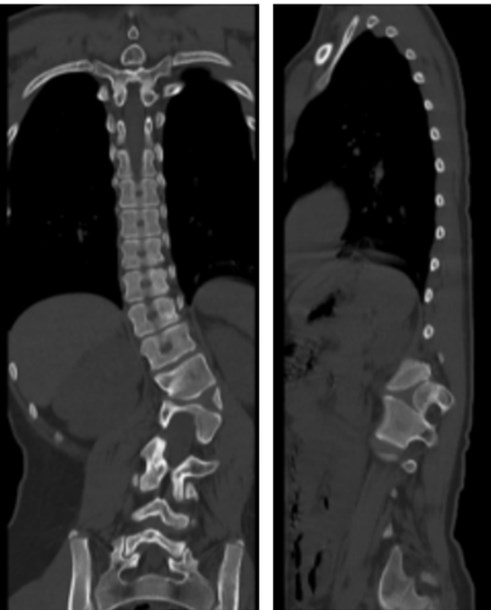

入院后,骨科二病区马延超主任医师诊断该患者胸腰段侧后凸畸形,腰1、腰2椎体形态失常,腰2椎体呈半椎体畸形改变。对于患者的情况,目前国际上公认的治疗方案是通过外科手术,完整切除半椎体,矫正局部畸形,重建脊柱的矢状面与冠状面平衡。

马延超团队结合患者的症状、体查情况、影像学资料,以及脊柱骨盆测量参数,为患者制订出个体化治疗策略和周密的手术方案。在手术置棒矫形过程中,由于局部侧后凸畸形,常规的置棒方式不但置棒困难,而且顶椎区域应力过大易造成矫形棒断裂或者螺钉松动,可能导致矫形丢失,畸形进展,需二次手术翻修。

马延超采用国际上先进的矫形理念,采用半椎体整块切除技术联合多棒序贯矫形技术,短棒负责矫正局部畸形,长棒负责矫正区域畸形和整体平衡,化整为零,分段矫形,不但大大提高了矫形的安全性和有效性,还有效降低了术后并发症,获得满意的临床效果。